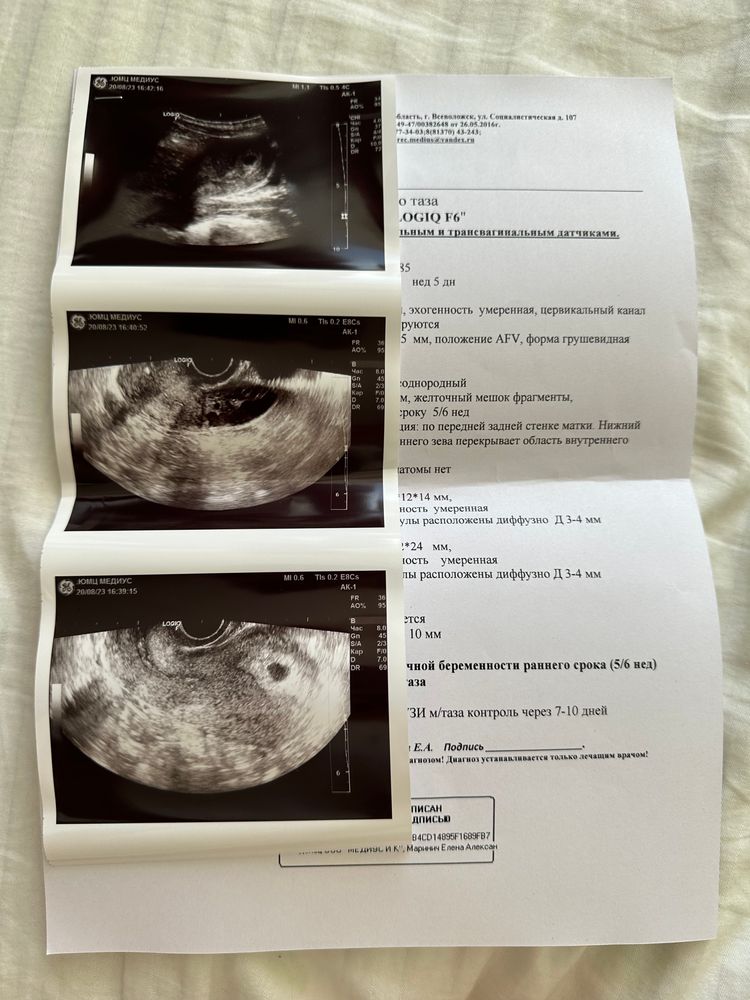

Виктория, беременность подтверждена, просто отстает по срокам, если овуляция на 15 день Изображение Изображение Но надежда умирает последней, через неделю точно узнаю, нормальная или нет беременность